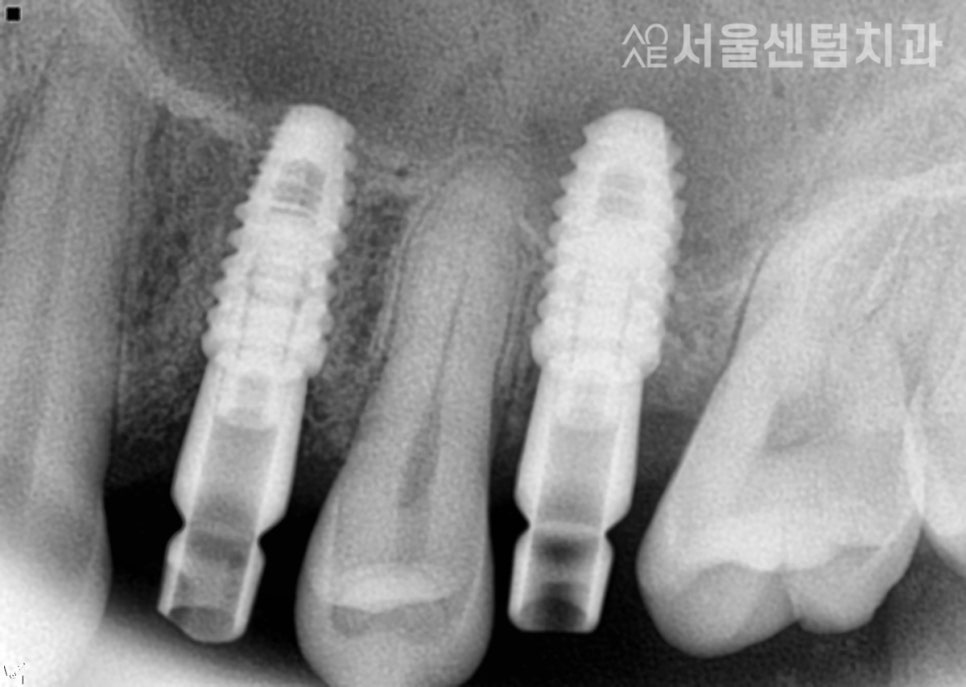

일단 이 분의 경우엔 뼈이식도 진행하였고

잇몸 상태가 좋지 않았기 때문에

충분히 기다리는 시간이 필요했습니다.

또한 2차 수술도 필요한 케이스로

2차수술 직전에 CT를 촬영하여

잇몸뼈가 잘 형성되었는지 확인 후

진행을 했습니다.

개인에 따라서 경과를 지켜보는 기간이 다르며

이 분은 4개월 후에 보철물을 제작하기로 했습니다.